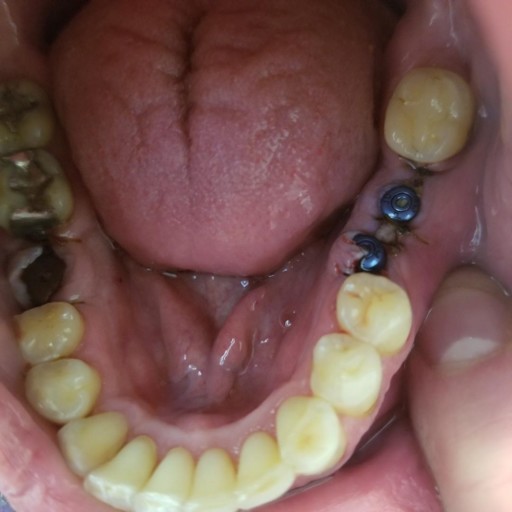

How long after socket grafting can you still get implants? When does the socket graft begin to fall out? I went from top x-ray to bottom in about 3 years. Was just wondering if I had done the grafting would it be this bad?

After a tooth is removed and a bone graft is placed, it is the standard of care to wait approximately 4-6 months prior to having the implant placed.  Every patient is as unique as their medical history.  Medications and other medical conditions may effect healing.  Once the bone or socket graft has fully integrated with the surrounding natural bone, the implant surgery can be scheduled.  After the implant is placed, it is necessary to then allow it to integrate with the bone prior to restoring it with a crown.  If care is taken after surgery, socket grafts are usually predictable and successful, however they sometimes can fail, making an unsatisfactory environment for implant placement.